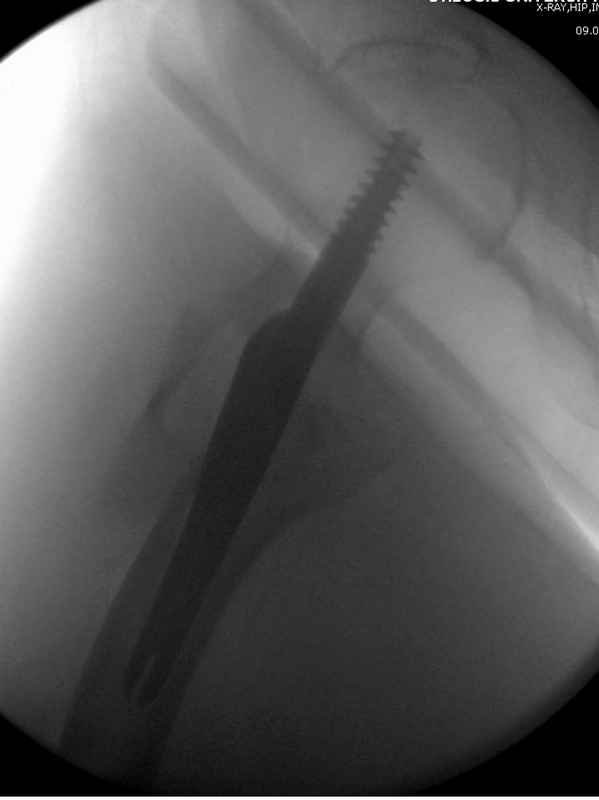

Здесь 83 года, травма в результате падения

судя по картинкам с ЭОПа явно использовались приемы непрямой репозиции под его контролем, а так же интраоперационный ЭОП-контроль положения винтов, без такого контроля операция может ухудшить ситуацию (опять же учтите сроки) т.к. результат буде зависеть в большей степени от искусства хирурга, а не от технологии